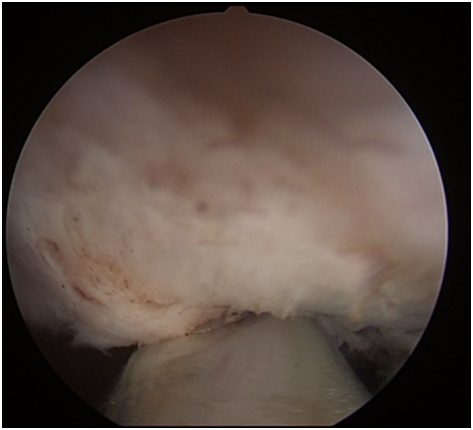

沿前列腺包膜剜除